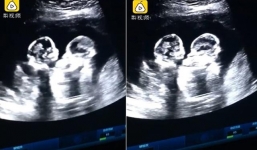

Cặp song sinh gây sốt mạng xã hội khi đánh nhau chí choé trong bụng mẹ